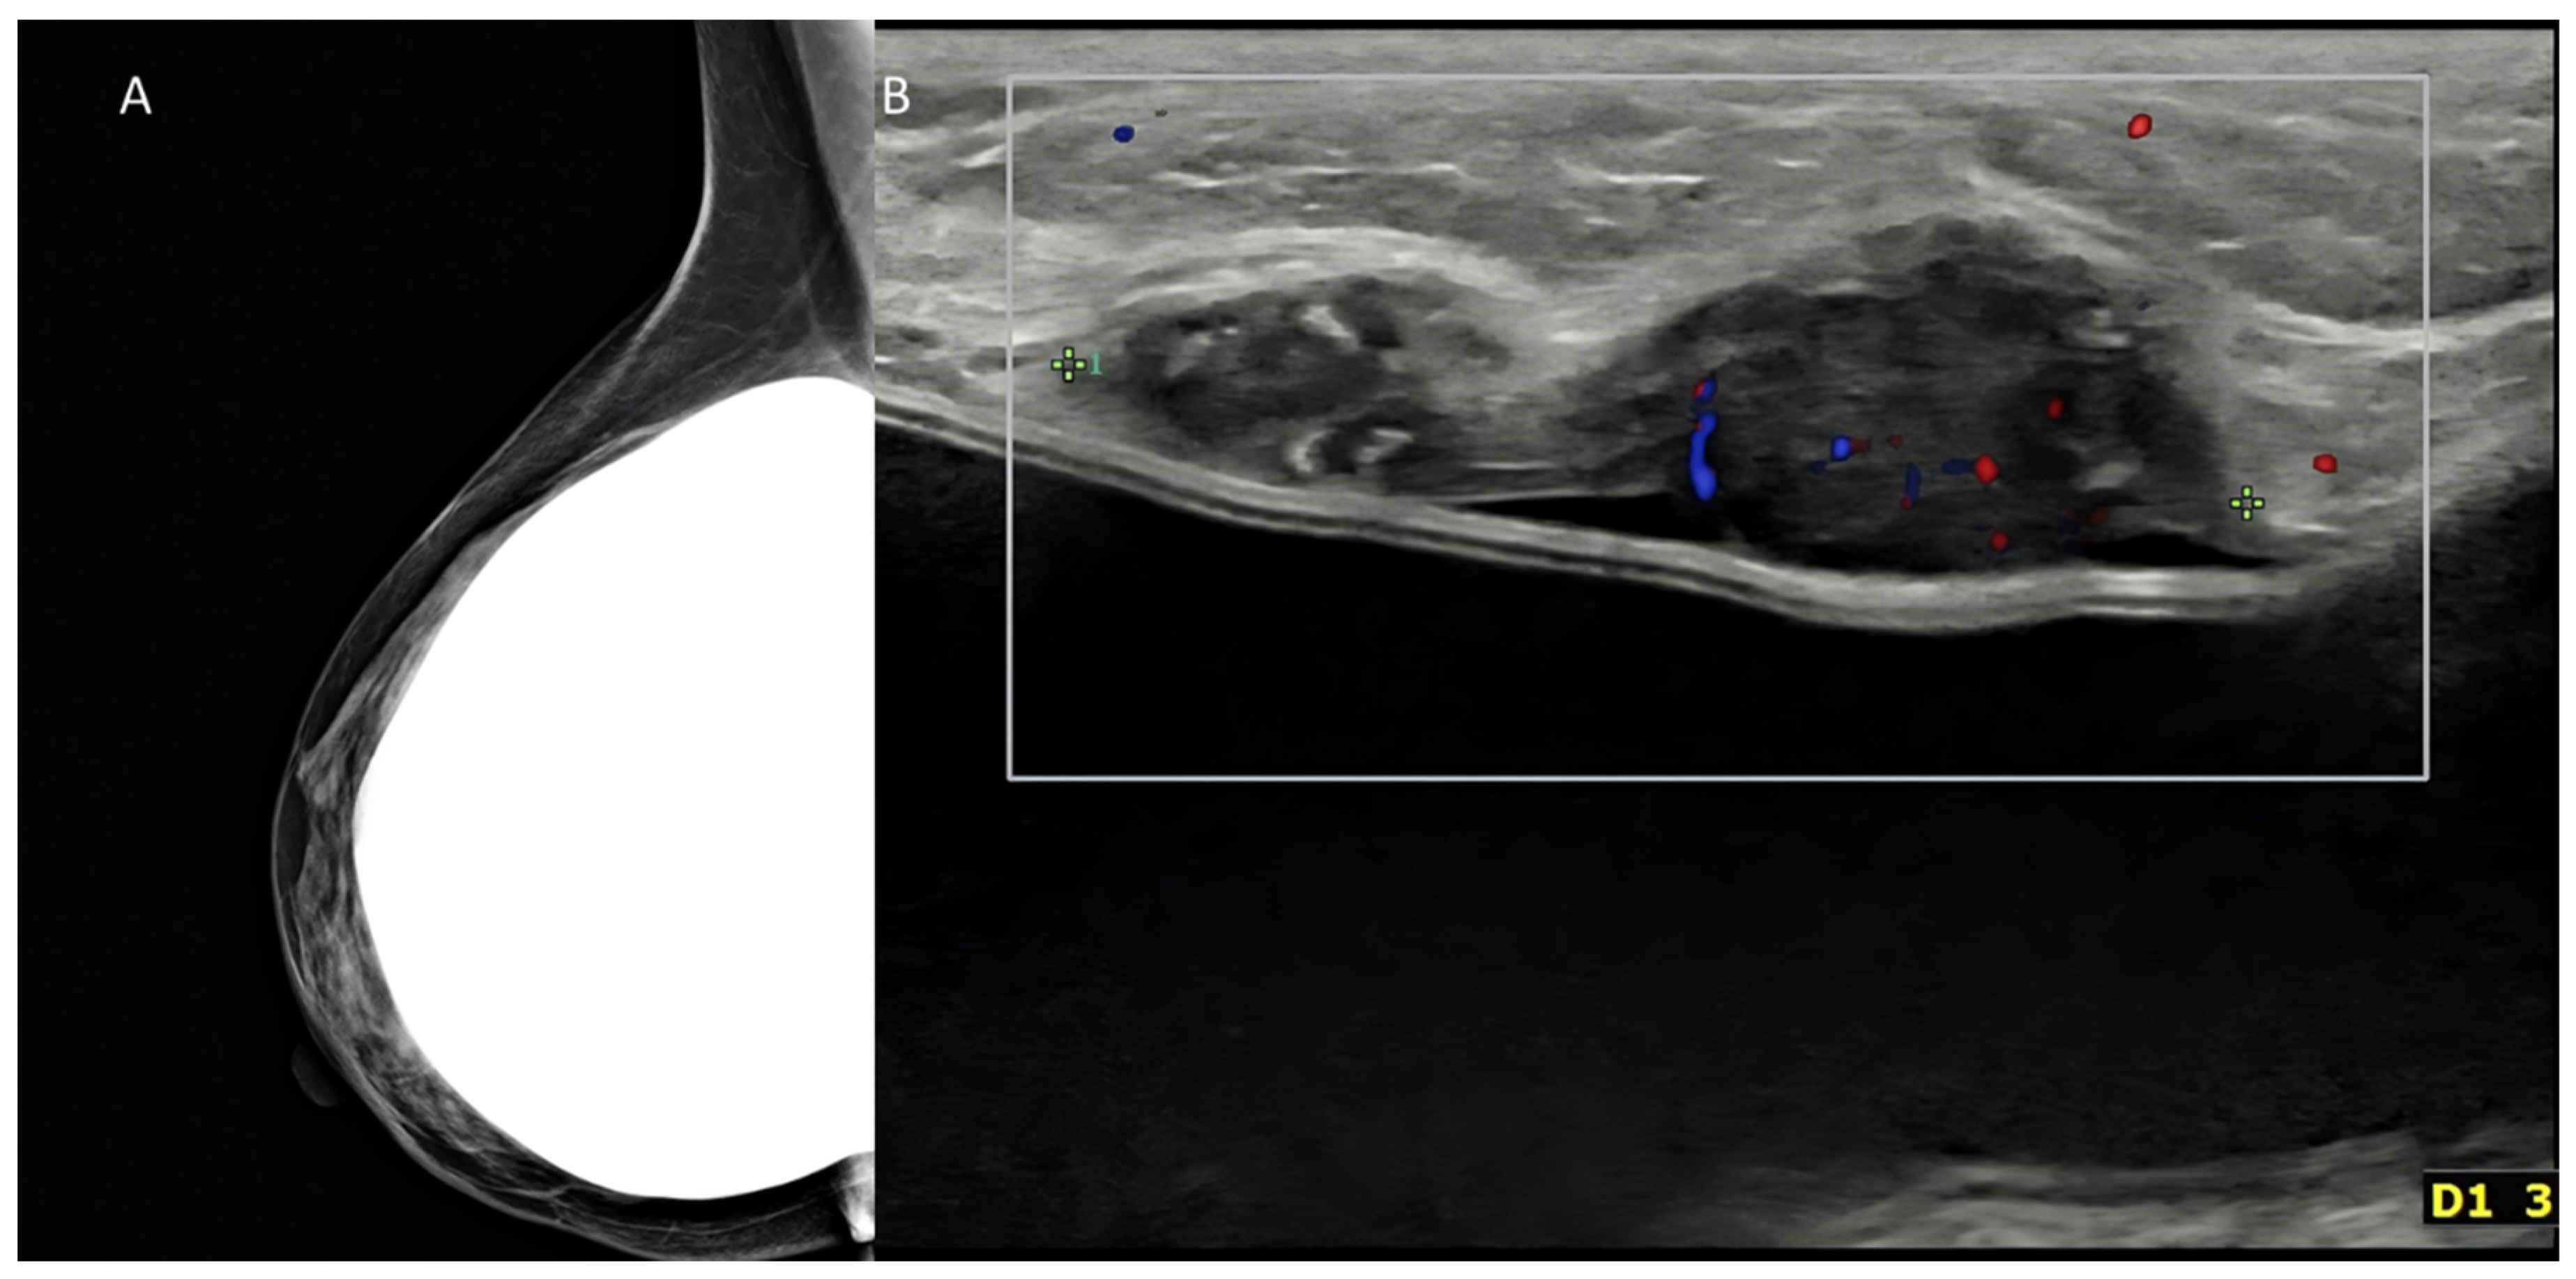

Figure 10. Palpable mass in a woman with history of augmentation mammoplasty. (A) Mammography oblique digital view was negative in this case, despite use of tomosynthesis. (B) US could detect a nodule immediately above the implant. The tumor proved to be a triple-negative invasive ductal carcinoma at surgery.

US works well for newborns, children, and adolescents with breast abnormalities (grading of premature thelarche, etc.). Breast disorders in pregnancy should be studied using US, at least because of radioprotection needs [11]. Lactating breasts are also difficult to image with mammography because of the glandular density, and US is the primary imaging modality in women with abnormal symptoms during lactation [11]. Male breast abnormalities should be studied with US, which can easily differentiate gynecomastia from cancer. Breast assessment in women scheduled for augmentation surgery or for hormonal therapy because of infertility is also based on US, particularly for younger women. Periodic assessment after mastoplasty is carried out with US, while MRI is employed when an implant rupture is suspected [110] (Figure 8).

US is both an adjunct and a complement to mammography (Figure 10).